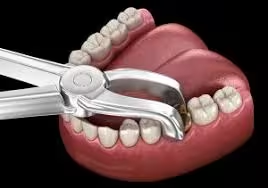

Emergency Extractions

We understand that dental emergencies can happen unexpectedly and often come with severe pain or discomfort. Our team is fully equipped to provide prompt, safe, and compassionate emergency tooth extractions when a tooth is severely decayed, infected, broken, or impacted and cannot be saved. We prioritize your comfort by using advanced techniques and local anesthesia to ensure the procedure is as pain-free and stress-free as possible. After the extraction, we provide clear post-operative care instructions and discuss options for tooth replacement, such as implants or bridges, if needed. Whether you're in sudden pain or have suffered dental trauma, we’re here to offer immediate relief and expert care—helping you return to comfort and health quickly.